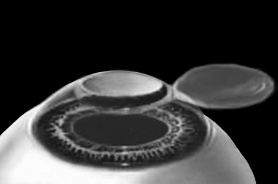

ЛАСИК – основной метод лазерной коррекции в мире в настоящее время. По большому счету, ФРК и ЛАСИК – единственные методы коррекции. Остальные методы являются либо модификациями ФРК и ЛАСИК, либо «компромиссом» между ними. Эпителий роговицы не трогают, так как он – залог быстрого заживления. Накладывают на глаз вакуумное кольцо – стальную присоску кольцевидной формы с присоединенной к нему трубочкой. Через трубочку из присоски отсасывается воздух, чтобы создать относительный вакуум. Отсасывает воздух главный аппарат для проведения ЛАСИКа – микрокератом. Это прибор размером с коробку из-под обуви. Его предназначение – срезание поверхностной крышки роговицы. К глазу присоединяют вакуумное кольцо, окружающее роговицу. Глаз четко фиксируется относительно кольца и сдвинуться с места может только с кольцом, в отверстие которого выступает купол роговицы. Затем к кольцу присоединяется головка микрокератома. Это второй инструмент микрокератома и соединяется с ним или шнуром, или тонким шлангом. Головка крепится на турбине, и вместе они имеют вид толстой шариковой ручки с обрубленным концом. Эту «ручку» хирург держит в правой руке, а вакуумное кольцо – в левой. Эта «ручка» нужна, чтобы сформировать крышечку роговицы. Внутри головки есть очень острое одноразовое лезвие. Турбина, соединенная с головкой, может двигать одноразовое лезвие туда-сюда, пилящими движениями. Можно резать роговицу, как хлеб, – пилящими движениями. И тут самое главное – скорость. Одноразовое лезвие делает 15000 пилящих движений в минуту. При такой скорости назвать это срезанием роговицы уже трудно, скорее это отслаивание верхних слоев. ![]() Рис. 3. Схема формирования роговичного лоскута с помощью микрокератома. Иллюстрация с сайта Международного лазерного центра www.optics.ru Итак, головка присоединяется к вакуумному кольцу и по специальным полозьям двигается над куполом роговицы (рис. 3). Срез, или отслаивание (называйте, как хотите), проводится не полностью, у крышечки (роговичного лоскута) остается маленький участок на периферии, соединяющий ее с роговицей (рис. 4). ![]() Рис. 4. Роговичный лоскут сформирован. Иллюстрация с сайта Международного лазерного центра www.optics.ru После формирования роговичного лоскута убирают инструменты микрокератома, затем шпателем откидывают его вбок (рис. 5). Обнажается роговичное ложе, то есть место, на котором лежал лоскут. Это верхние слои стромы роговицы. Ложе осушают тупфером и так же, как и при ФРК, настраивают лазер и испаряют несколько микрон вещества стромы (рис. 6). Потом промывают строму водой и шпателем укладывают лоскут на место. ![]() Рис. 5. Роговичный лоскут откинут в сторону. Иллюстрация с сайта Международного лазерного центра www.optics.ru ![]() Рис. 6. Луч эксимерного лазера испаряет на роговичном ложе несколько микрон стромы роговицы. Иллюстрация с сайта Международного лазерного центра www.optics.ru Стоит один раз моргнуть и лоскут скомкается и зрения не будет. Его бы пришить на место. Но швы деформируют роговицу. Все проще. Лоскут разглаживают мокрым тупфером, прижимая его ровненько к старому месту (рис. 7 и 8). Только место не старое, с роговичного ложа удалили несколько микрон в виде причудливой ямки (при коррекции близорукости). ![]() Рис. 7. При коррекции близорукости на роговичном ложе формируется «ямка». Иллюстрация с сайта Международного лазерного центра www.optics.ru ![]() Рис. 8. Роговичный лоскут укладывается на место. Иллюстрация с сайта Международного лазерного центра www.optics.ru Края роговичного лоскута осушают сухим тупфером. Влага, оставшаяся под лоскутом в ямке роговичного ложа, высасывается в тупфер. Лоскут притягивает к ложу, как вакуумную присоску. Вакуумом начали, вакуумом закончили. Ждем, когда закончится приживление лоскута к ложу. Эпителий цел и невредим. А значит, никаких болей. Около трех часов возможны слезотечение и светобоязнь. И все (рис. 9). ![]() Рис. 9. Форма роговицы до проведения коррекции (а) и после коррекции близорукости (б). Испарение нескольких микрон толщины роговицы привело к уменьшению ее кривизны в центре. Иллюстрация с сайта Международного лазерного центра www.optics.ru Хирурги о ЛАСИКе говорят: «90 % хирургии и 10 % долечивания». Лазерный субэпителиальный кератомилез (LASEK) Модификация ФРК. Чтобы укоротить неприятный послеоперационный период, эпителий, обработанный спиртовым или солевым раствором, отслаивают очень бережно, с помощью специальных инструментов, в виде цельного лоскута. А после испарения эксимерным лазером боуменовой мембраны и нужного количества слоев стромы этот эпителиальный лоскут укладывают обратно и, чтобы он не сместился, прижимают мягкой контактной линзой. Через 3–4 дня эпителий заживает, а благодаря линзе и даже еще не приживленному эпителиальному лоскуту боль и светобоязнь не беспокоят пациента с первых часов после коррекции, а зрение восстанавливается на пару недель быстрее, чем при ФРК. Также одной из модификаций ФРК является MAGEK. Основным отличием от ФРК является применение препарата Митомицин С (Mitomycin-С), который блокирует «слишком быстрое деление клеток» и снижает риск возникновения хейза. Эпи-ЛАСИК (Epi-LASIK) Нечто среднее между ЛАСИК и LASEK. Для отделения эпителия используются не спиртовой или солевой растворы, а специальный аппарат, очень похожий на микрокератом. Аппарат называется эпикератомом. Он отслаивает эпителий вместе с частью боуменовой мембраны в виде лоскута, похожего на лоскут при ЛАСИКе, только гораздо тоньше. После проведения коррекции лоскут также прижимают контактной линзой. Но не поврежденный химическим ожогом эпителиальный лоскут, да еще с остатками боуменовой мембраны, значительно сокращает период заживления и восстановления и снижает другие недостатки ФРК и LASEK, о которых будет сказано ниже. Рефракционный эксимерлазерный интростромальный кератомилез (РЭИК) |